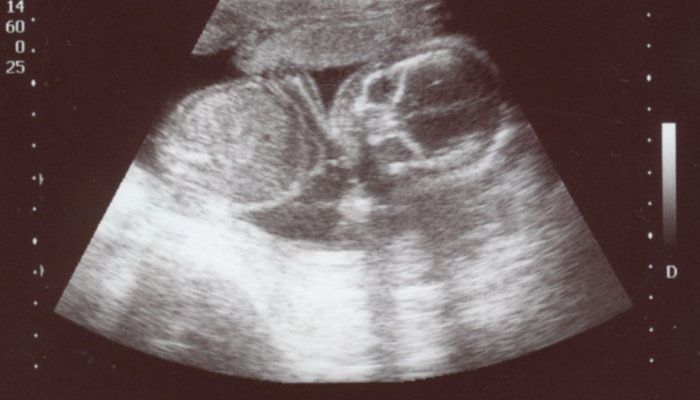

犬飼ねこさんの妊娠18週目のエコー写真

手の指がはっきりと見えます。